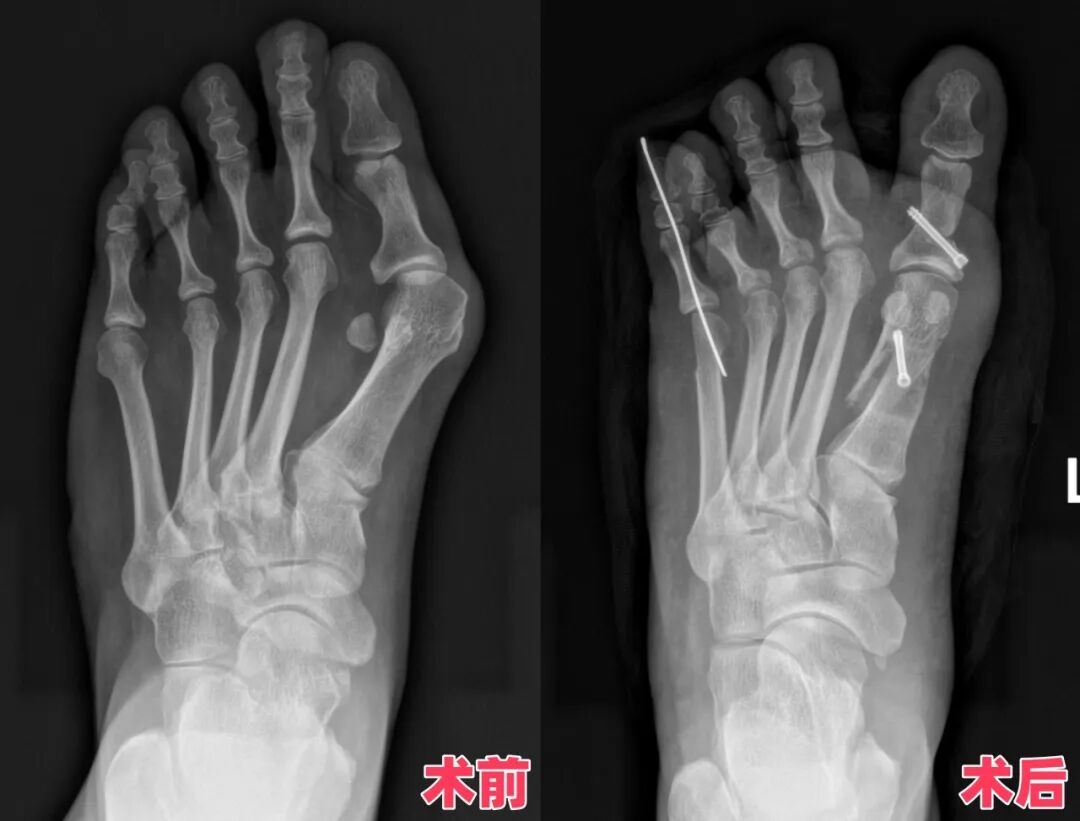

告别“大脚骨”!穿不了凉鞋的遗憾终圆满